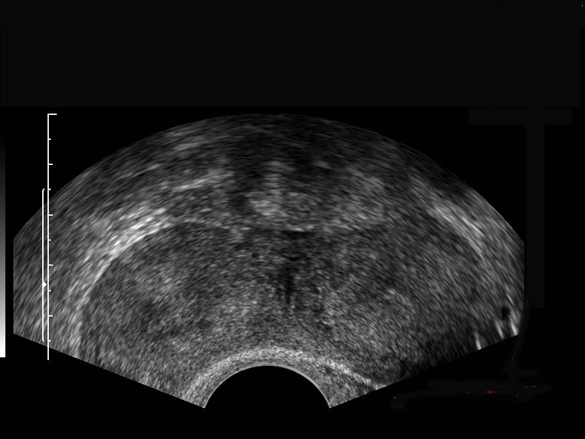

Utérus bicorne (corporéal)